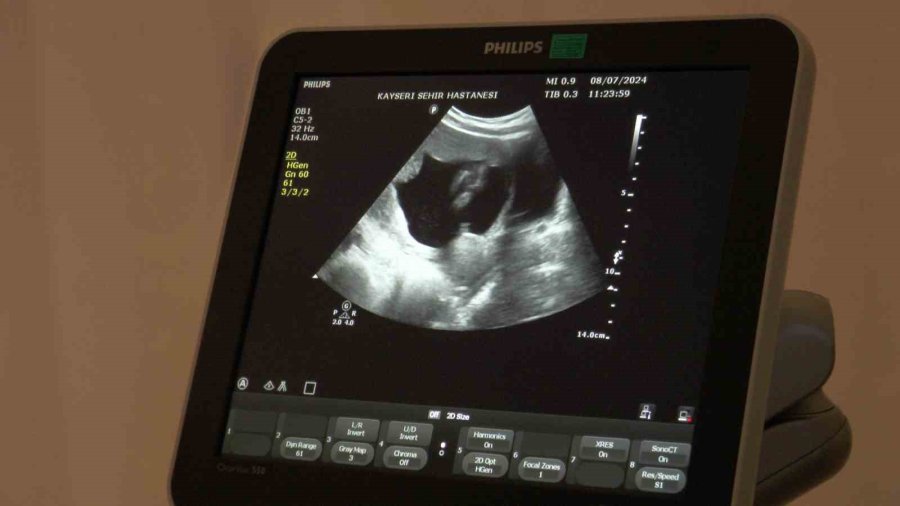

Kayseri'de yaşayan 1 çocuk annesi 35 yaşındaki S.D., ikinci kez anne olmak istedi. Fakat gittiği hastanelerde doğal yolla hamile kalmasının çok zor olduğu ve tüp bebek tedavisine yönelmesi gerektiği söylendi. En sonunda Kayseri Şehir Hastanesi'ne başvuran 35 yaşındaki S.D.'ye, doktorlar tarafından tüp bebek yönteminden önce tetkikler yapıldı. Kayseri Şehir Hastanesi Kadın Hastalıkları ve Doğum Kliniği Tüp Bebek Ünitesi'nde yapılan tetkiklerde daha önce düşük ve dış gebelik geçiren kadının rahim tüplerinden birinde tıkanma ve iltihaplanma olduğu tespit edildi. Yapılan ameliyat ile tıkalı tüpü alınan ve iltihapları temizlenen S.D., doğru tedavi yöntemi sayesinde tüp bebek ile değil doğal yolla kısa sürede ikinci çocuğuna gebe kaldı.

Doç. Dr. İlknur Çöl Madendağ,merkezde hastaya tedavi uygulamadan önce planlamaları yaparak bilgilendirdiklerini ve ortak karar ile tedavi uyguladıklarını söyleyerek, "Aslında hastalarımızın çoğu merkezimize tüp bebek yaptırma istemi ile gelmekte ama biz hastalarımızı değerlendirdikten sonra durumları hakkında ayrıntılı bilgi verip, tabi son tercihi onlara bırakmakla beraber, bilimsel veriler ışığında tıbbi durumu ne gerektiriyorsa öncelikle onu öneriyoruz hastalarımıza. Öncelikle tıbbi durumu hakkında hastalarımızı bilgilendirip önerimizi yapıyoruz ve onun isteği ile ortak kararımızı verip tedavimizi uyguluyoruz. Burada da hastamızın azalmış yumurtalık rezervi dediğimiz yumurta sayısı azlığı ve geçirilmiş dış gebelik, düşük, rahim tüp iltihabı, enfeksiyon durumları gibi sıkıntıları vardı. Bize geldiğinde önce ayrıntılı muayenesini yapıp gerekli tetkiklerinin ardından cerrahi müdahalesini planladık. Hastamızın azalmış yumurta sayısı vardı ama öncelikle rahim tüp filmini çektiğimize tüplerinde sıvı toplaması olduğunu ve kapalı olduğunu gördük. Yaptığımız ameliyatta tüpünün tıkalı olduğunu teşhis edip o sıvı toplamış tüpü aldık. Diğer tüpünün açık olduğunu gördükten sonra enfeksiyon tedavisini de yaptık. Yumurtalık gelişimini ve zamanlamasını ayarlayarak tüp bebek tedavisine gerek kalmadan gerekli antibiyotedavisini de verdikten sonra spontan gebeliğe 2 ay gibi kısa bir zaman içinde ulaştık. Geçirilmiş iltihabı vardı ve buna bağlı dış gebeliğinin oluştuğu yerde sıvı toplaması vardı. Bu da engel olan bir durumdu. Sonrasında hastamızın yumurta sayısını tekrar saydık. Gerekli destek tedavilerini verdik ve gebeliğine ulaştık. Şu an 16 haftalık gebeliği mevcut ve sağlıklı bir şekilde gidiyor" dedi.